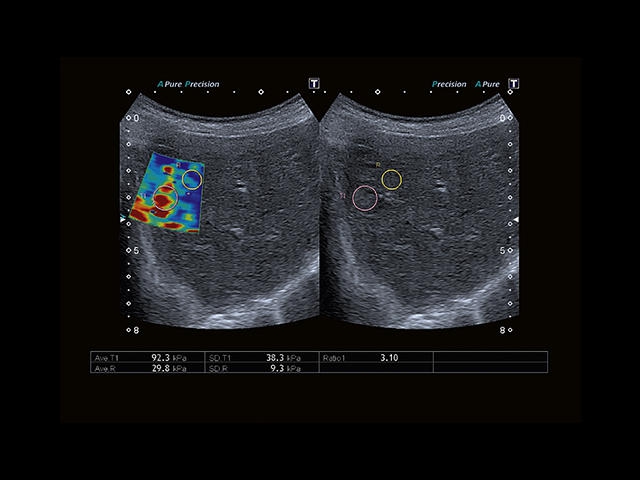

Обновленная версия легендарного УЗ-сканера. Стационарный аппарат экспертного класса Aplio 500 Toshiba NEW, визуализирует анатомические структуры в высоком разрешении. Модель позволяет выявить микрокальцификаты, новообразования, нарушения в работе сердца, сосудов и мышц. Присутствует функция виртуальной эндоскопии, 4D-сканирования, эластометрии тканей, УЗИ с контрастированием. За повышение качества изображения отвечают технологии ApliPure и Superb Microvascular Imaging. Первая задействует возможности пространственного и частотного кодирования, формирует цельный визуальный ряд с сохранением клинических маркеров. Вторая улучшает отображение микрососудистого русла, используя доплеровский эффект. Модель оснащена 21-дюймовым монитором, имеет 4 активных порта. Возможно подключение педиатрических, интраоперационных, лапароскопических и чреспищеводных датчиков.

Компрессионная

Компрессионная эластография:

Эластография сдвиговой волной/Эластометрия: